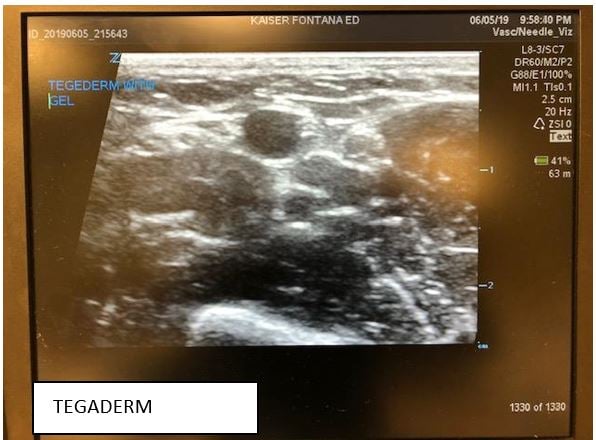

Recently, the ultrasound community has seen a great debate spanning across various social media outlets, email, and academic arenas about the use of Tegaderm and its potential for damaging and degrading the rubber surface of the ultrasound probe over time. For many of us, we can remember our early days of residency when ultrasound-guided IVs first came into practice. Many people may not have even used a Tegaderm when first learning how to do this technique. Later, they discovered that covering the probe surface with a tegaderm or using sterile/nitrile gloves as a probe cover provided a cleaner surface than doing the IV line with just gel and the probe alone.1,2 This cleaner method was also more cost-effective than using the more commercially-available sterile probe covers. However, in the last year, there has been increasing concern regarding the potential risks associated with using a Tegaderm.

Parker labs introduced the UltraDrape an affordable, sterile dressing that acts as a barrier against contamination. Since a probe cover is not required, gel is placed on the top surface of the dressing, separating the probe from the sterile gel-free puncture site. This top layer is later removed and the remaining adhesive layer below acts to secure the IV reducing clean up time, contamination, and mess associated with excess gel. However, this product requires that you view and mark where you will be inserting the IV before placing the UltraDrape down since it can’t be moved once you set it down. Views of the vessel on the machine are comparable to using tegaderm and it costs $2.50 per dressing.

The next product, by SHEATHES, is an antiviral, non-sterile adhesive probe cover costing approximately $1.85 per cover. It does not require the use of gel on the interface between the surface of the probe and the cover, but still requires sterile gel on the surface of the skin. The adhesive surface does not leave a sticky residue and is stated to cause no damage to the rubber surface of the probe cover. Also, there is no risk of air bubbles which can cause artifact and distort the image. The entire cover is tested for leaks and has small enough pores that prevent infections by pathogens up to 20 nm small. There are options for just the adhesive patch, an 8 inch cover ($1.30 each) and longer sterile central line style adhesive probe covers ($7 to $10). Each of these have a three-year shelf life. Of note, you may need more than one size as the adhesive surface varies. The view of the vessel is good but you may need to turn gain down a bit more than when you use tegaderm or glove.